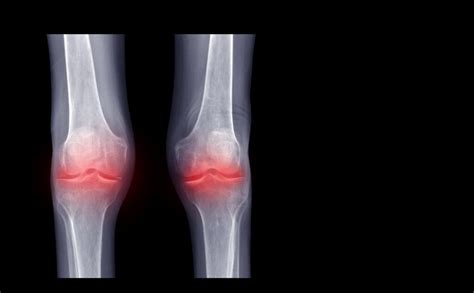

Alright, so Pseudogout , the star of our show, is a type of arthritis. Don’t worry, it’s not as scary as it sounds. Essentially, it happens when calcium pyrophosphate dihydrate (CPPD) crystals form in your joints. Think of these crystals as tiny, sharp needles that get lodged in the joint. These crystals then trigger inflammation, leading to sudden and painful attacks. Common symptoms include intense joint pain, swelling, and warmth in the affected area. The pain can come on quickly and be pretty severe, often mimicking the symptoms of gout (hence the name “pseudogout,” meaning “false gout”). Usually the knee is the main location, but it can also affect other joints like the wrist, ankle, elbow, shoulder, and even the small joints of the hand and feet. The episodes of pseudogout can last for days or even weeks. It’s crucial to seek medical attention if you suspect you have pseudogout, as proper diagnosis and treatment are essential for managing the symptoms and preventing long-term joint damage. Early diagnosis and treatment can significantly improve your quality of life, allowing you to get back to enjoying your day-to-day activities.

So, what happens if you think you have Pseudogout ? First off, you’ll need to see a doctor. They’ll start by asking about your symptoms and medical history. Expect them to inquire about your joint pain, its intensity, where it is located, and how long you’ve been experiencing it. They will probably perform a physical examination to check for swelling, tenderness, and range of motion in your joints. The most reliable way to diagnose pseudogout is through a procedure called joint aspiration , where the doctor uses a needle to draw fluid from the affected joint. This fluid is then examined under a microscope to look for those distinctive CPPD crystals. X-rays can be used to reveal the presence of calcium deposits in the cartilage, which can suggest pseudogout. Blood tests will be done to rule out other conditions and assess the levels of inflammatory markers. Sometimes, other tests are needed, depending on your individual symptoms and medical history. The combination of your medical history, physical examination, and lab results will allow the doctor to confirm the diagnosis.